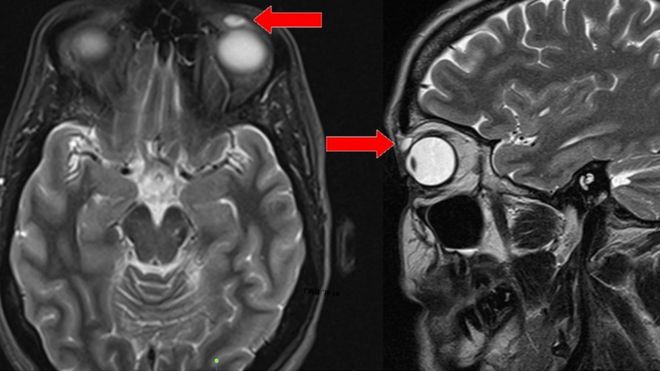

A scan showed the cyst above the woman's eye

Researchers at Ninewells hospital carried out an MRI scan after the woman was referred to the Department of Ophthalmology by her GP.

The patient presented with left upper eyelid swelling and ptosis (a droopy eyelid), according to doctors Sirjhun Patel, Lai-Ling Tan, and Helen Murgatroyd .

Images revealed an ovoid-shaped cyst about 8mm long but there was no evidence of anything inside it.